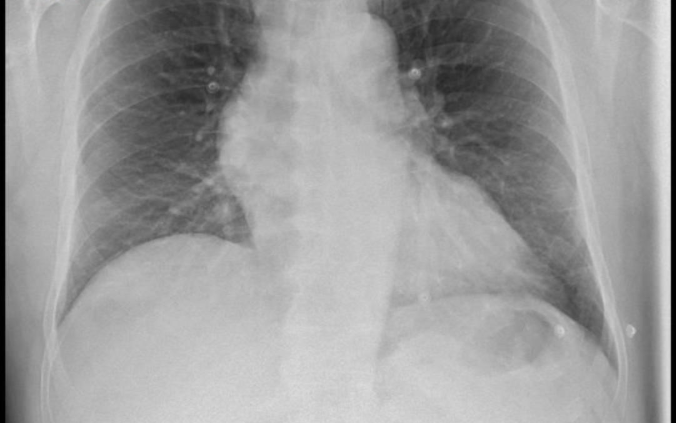

Sin embargo, pese a que la radiografía de tórax mostraba, según el informe pericial presentado por la familia, un ensanchamiento mediastínico y un aumento del tamaño de la silueta de la aorta ascendente, el paciente fue dado de alta a las 16.48 horas con el diagnóstico de gastroenteritis aguda (GEA) y tratamiento analgésico.

Según la reclamación, dicha radiografía ni siquiera fue mencionada en el informe de alta hospitalaria, a pesar de que el paciente continuaba con el mismo dolor intenso que había motivado su ingreso.

Según el perito, existió un fallo en la valoración radiológica al no interpretarse correctamente una radiografía de tórax que mostraba un marcado ensanchamiento mediastínico y una dilatación patológica de la aorta ascendente, un hallazgo altamente sugestivo de disección aórtica. A ello se sumó, según el escrito, la desestimación de signos clínicos de extrema gravedad, como el dolor toracoabdominal irradiado, la sensación presincopal y la presencia de una leucocitosis con neutrofilia, indicadores de un proceso agudo severo que obligaban a una vigilancia estrecha del paciente.

"La correcta valoración de la radiografía de tórax junto al cuadro clínico obligaba a sospechar una disección aórtica. No hacerlo y enviar al paciente a su casa con un diagnóstico trivial lo abocó a la muerte", afirma Arnaiz.